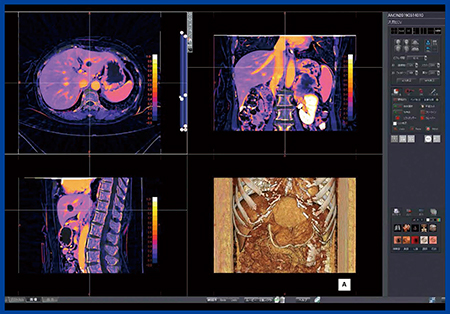

当院における,膵臓がんにおける予後予測因子としてECV解析の方法を図1に示す。基本的には,造影CTの平衡相と単純CTの腫瘍と血管にROIを置き,腫瘍の造影効果から血管の造影効果を除した値をヘマトクリット値で補正する。しかしながら,この手法は煩雑であり,測定誤差が非常に大きいという問題点がある。そこで,Ziostation2の“CT心筋ECV解析”を腹部に応用することを考えた。Ziostation2では造影CTの平衡相から単純CTのサブトラクション時に非剛体位置合わせを行うことで,位置ズレの少ない高精度の差分画像が瞬時に得られる。次に,差分画像上の血管にROIを設定し,ヘマトクリット値を入力するだけでECVマップが簡単に作成できる(図2)。

図2 Ziostation2による腹部のECV解析(W.I.P.)